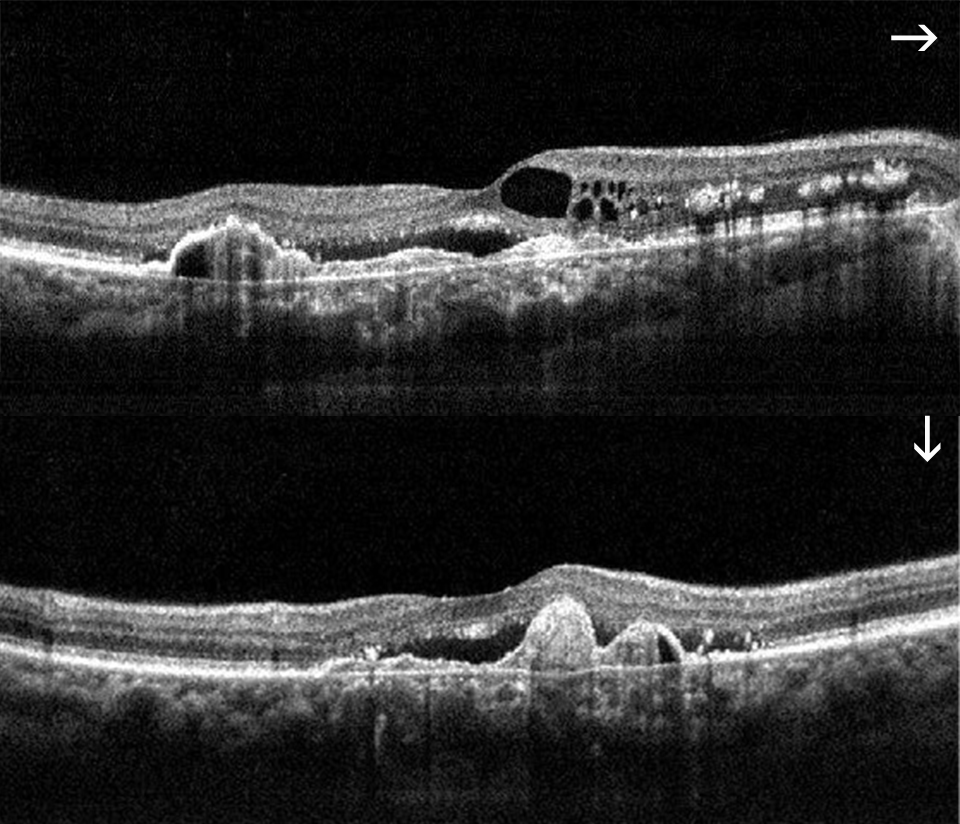

- Estudio de la mácula, estructura de la retina responsable de la máxima agudeza visual. La OCT nos permite realizar cortes histológicos de la retina, desde la cara anterior a la posterior y analizarla microscópicamente, permitiéndonos observar los cambios patológicos que produzcan. Es una prueba fundamental en el seguimiento de pacientes con Degeneración macular asociada a la edad (DMAE), edema macular diabético, edema macular secundaria a trombosis, agujero macular, membrana epirretiniana, tracciones vítreo-maculares, coroidopatía serosa central, etc.